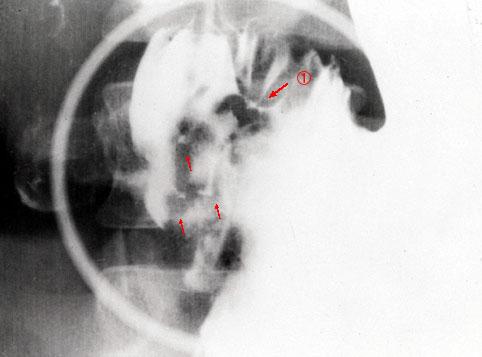

疾患(病理主体)の分類炎症性・潰瘍性疾患/クローン病

部位(臓器別)胃(部位)/前庭

検査方法X-P

病変の最大径(ミリ)10〜14